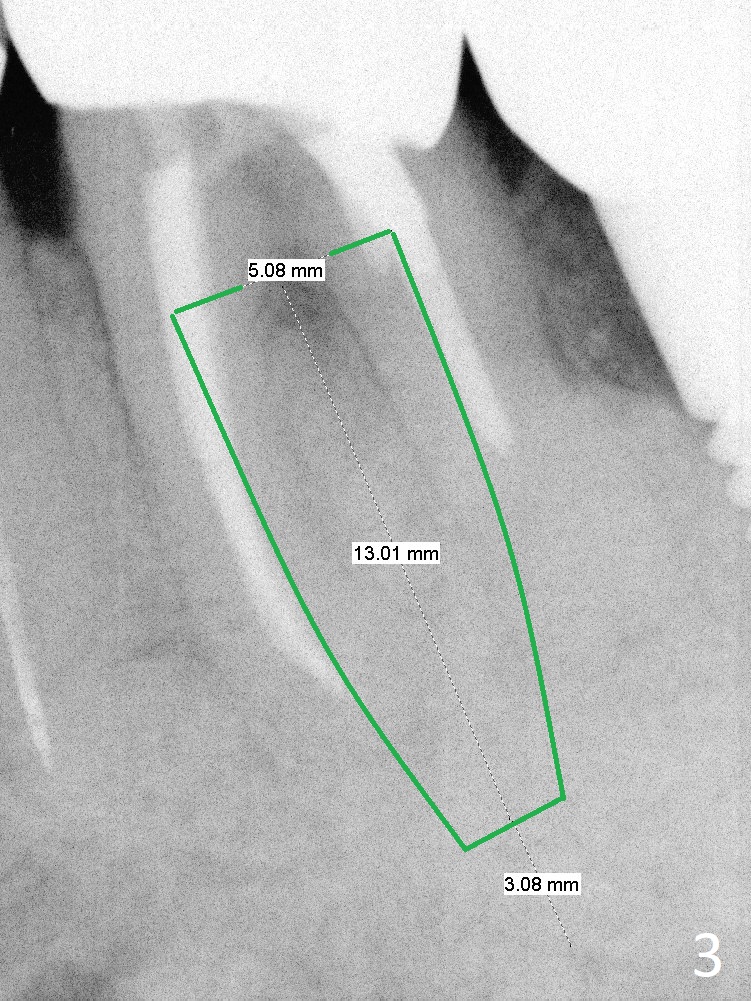

A 87-year-old man loses #19 crown and post recently (Fig.1).  A new implant system will be tried.  It has 2 main features.  There are 2 sets of drills (short and long).  Every time try short ones unless the neighboring teeth are extremely long.  There are several lengths of stoppers (as short as 5.7 mm) so that we do not have to use short stoppers from DIO Sinus Master Kit.  If a sample implant (5x10 mm, Fig.2) does not achieve primary stability, shift to UF, but still use IS drill for 13 mm (Fig.3).  Take preop PA.  Prepare surgical handpiece for sectioning.  Place bone graft to the defect between #18 and 19.